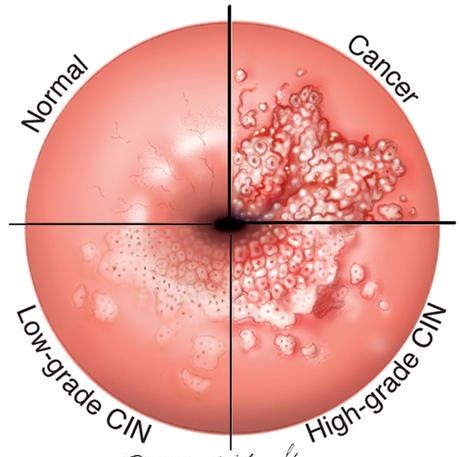

دیسپلازی مقعدی چیست؟

زگیلها پس از برداشته شدن برای بررسی به پاتولوژی فرستاده میشوند. برخی از زگیلها در زیر میکروسکوپ دچار تغییرات غیرطبیعی میباشند. به این تغییرات دیسپلازی مقعدی گفته میشود و با میکروسکوپ میتوان پیشرفت دیسپلازی یا تغییرات غیر طبیعی آنها را تعیین کرد. این تغییرات توسط پزشکان به نئوپلازی داخل اپیتلیومی با درجه بالا و درجه پایین تقسیم میشوند.

به سلول هایی که بدخیم یا پیش بدخیم میشوند، اما به عمق پوست حمله نمیکنند، نئوپلازی با درجه بالا گفته میشود. اگرچه این بیماری به احتمال زیاد پیشرونده به سرطان مقعد است، اما این سرطان مقعد نیست و متفاوت از سرطان مقعد درمان میشود.

دیسپلازی مقعد مشابه دیسپلازی دهانه رحم(نئوپلازی داخل اپیتلیومی دهانه رحم) است چرا که از یک عفونت مشابه ناشی از ویروس پاپیلومای انسانی منشا میگیرند و به ترتیب میتوانند به سرطان مقعد و گردن رحم پیشرفت کنند. بنابراین، بیماران مبتلا به دیسپلازی مقعدی نیاز به پیگیری دقیق توسط پزشک دارند تا هرگونه ضایعه جدید به سرعت ارزیابی شود. معاینه زنان و زایمان نیز در زنان توصیه میشود، زیرا وجود نئوپلازی داخل اپیتلیومی با درجه بالا، بیمار زن را در معرض خطر ابتلا به نئوپلازی داخل اپیتلیومی دهانه رحم نیز قرار میدهد.

چرا باید دیسپلازی مقعدی را درمان کنیم؟

هنگامی که دیسپلازی مقعد داشته باشید، بندرت خود به خود از بین میرود. اگرچه هنوز هم بسیار نادر است، اما خطر ابتلا به سرطان مقعد در بیماران با سابقه دیسپلازی مقعد (کمتر از 5%) کمی وجود دارد. به نظر میرسد پیشرفت آن در بیماران مبتلا به HIV مثبت بیشتر است. خطر پیشرفت به سرطان مقعد ممکن است در بین بیماران مبتلا به HIV مثبت 50 تا 10٪ متغیر باشد.

چگونه دیسپلازی مقعدی تشخیص داده میشود؟

دیسپلازی مقعد در زگیل مقعدی یا گاهی اوقات این تغییرات به طور اتفاقی در زمان جراحی مقعد غیرمرتبط (یعنی جراحی بواسیر) مشاهده میشود.

روشهای غربالگری موجود برای تشخیص دیسپلازی مقعدی شامل سیتولوژی مقعد و آنوسکوپی با وضوح بالا است. با این حال، این روشها به صورت جهانی انجام نمیشوند و نقش آن ها در مدیریت بیماران مبتلا به دیسپلازی مقعد در حال حاضر ناشناخته است.

سیتولوژی پاپ اسمیر مقعد شامل استفاده از سواپ مقعدی برای نمونه برداری از سلوله ای کانال مقعد است و میتواند برای غربالگری بیمارانی که دارای ریسک بالایی هستند و پیگیری پس از درمان دیسپلازی مقعدی مورد استفاده قرار بگیرد. متأسفانه، تا 45٪ جواب پاپ اسمیر مقعد بیماران برای دیسپلازی مقعدی ممکن است مثبت کاذب باشد. همچنین، مشخص نیست که آیا پاپ اسمیر مقعد نتیجه شما را بهبود میبخشد یا خطر ابتلا به سرطان مقعد را کاهش میدهد یا خیر.

آنوسکوپی با وضوح بالا به طور معمول شامل استفاده از رنگ های حاجب موقت (اسید استیک 3% و محلول ید لوگوول) داخل کانال مقعد است که به دنبال آن ارزیابی با میکروسکوپ با وضوح بالا انجام می شود تا به تشخیص بافت طبیعی از غیر طبیعی کمک کند. این روش بسیار شبیه به کولپوسکوپی (معاینه دهانه رحم) در خانمهایی است که دیسپلازی گردن رحم دارند. بیوپسیهای مسقیم از نواحی مشکوک و نیاز به درمان باید انجام شود.